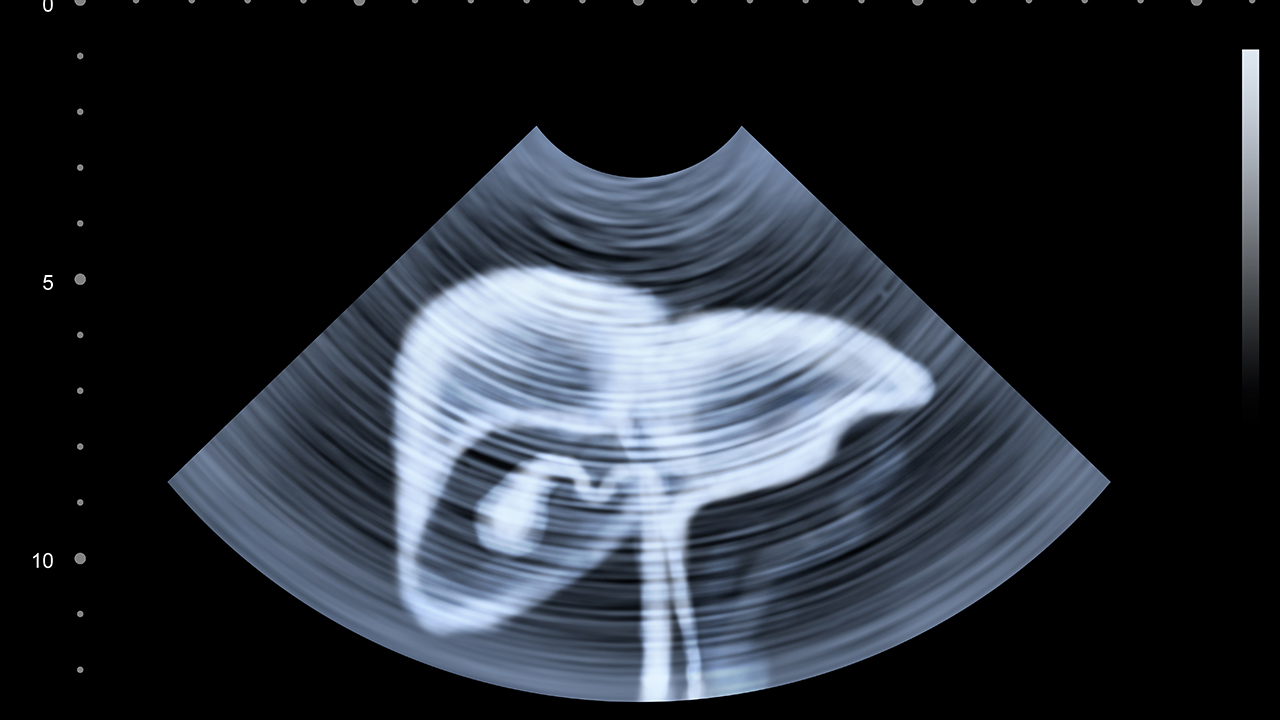

肝癌是一种常见的恶性肿瘤,其发病原因复杂,包括病毒性肝炎、肝硬化、长期酗酒、黄曲霉素污染等。早期肝癌症状不明显,因此定期体检和早期筛查尤为重要。目前肝癌的治疗方法包括手术切除、肝移植、射频消融、介入治疗、靶向治疗和免疫治疗等,患者应根据病情选择合适的治疗方案。

肝癌的预防与健康管理至关重要。对于高危人群,如慢性乙肝、丙肝患者及肝硬化患者,应定期进行肝脏超声和甲胎蛋白检测,以便早期发现肝癌。日常生活中应避免酗酒、减少黄曲霉素污染食物的摄入,并积极控制肝炎病毒感染。对于已确诊的肝癌患者,应严格遵循医嘱,定期复查,保持良好的生活习惯,合理膳食,适当运动,以提高治果和生活质量。